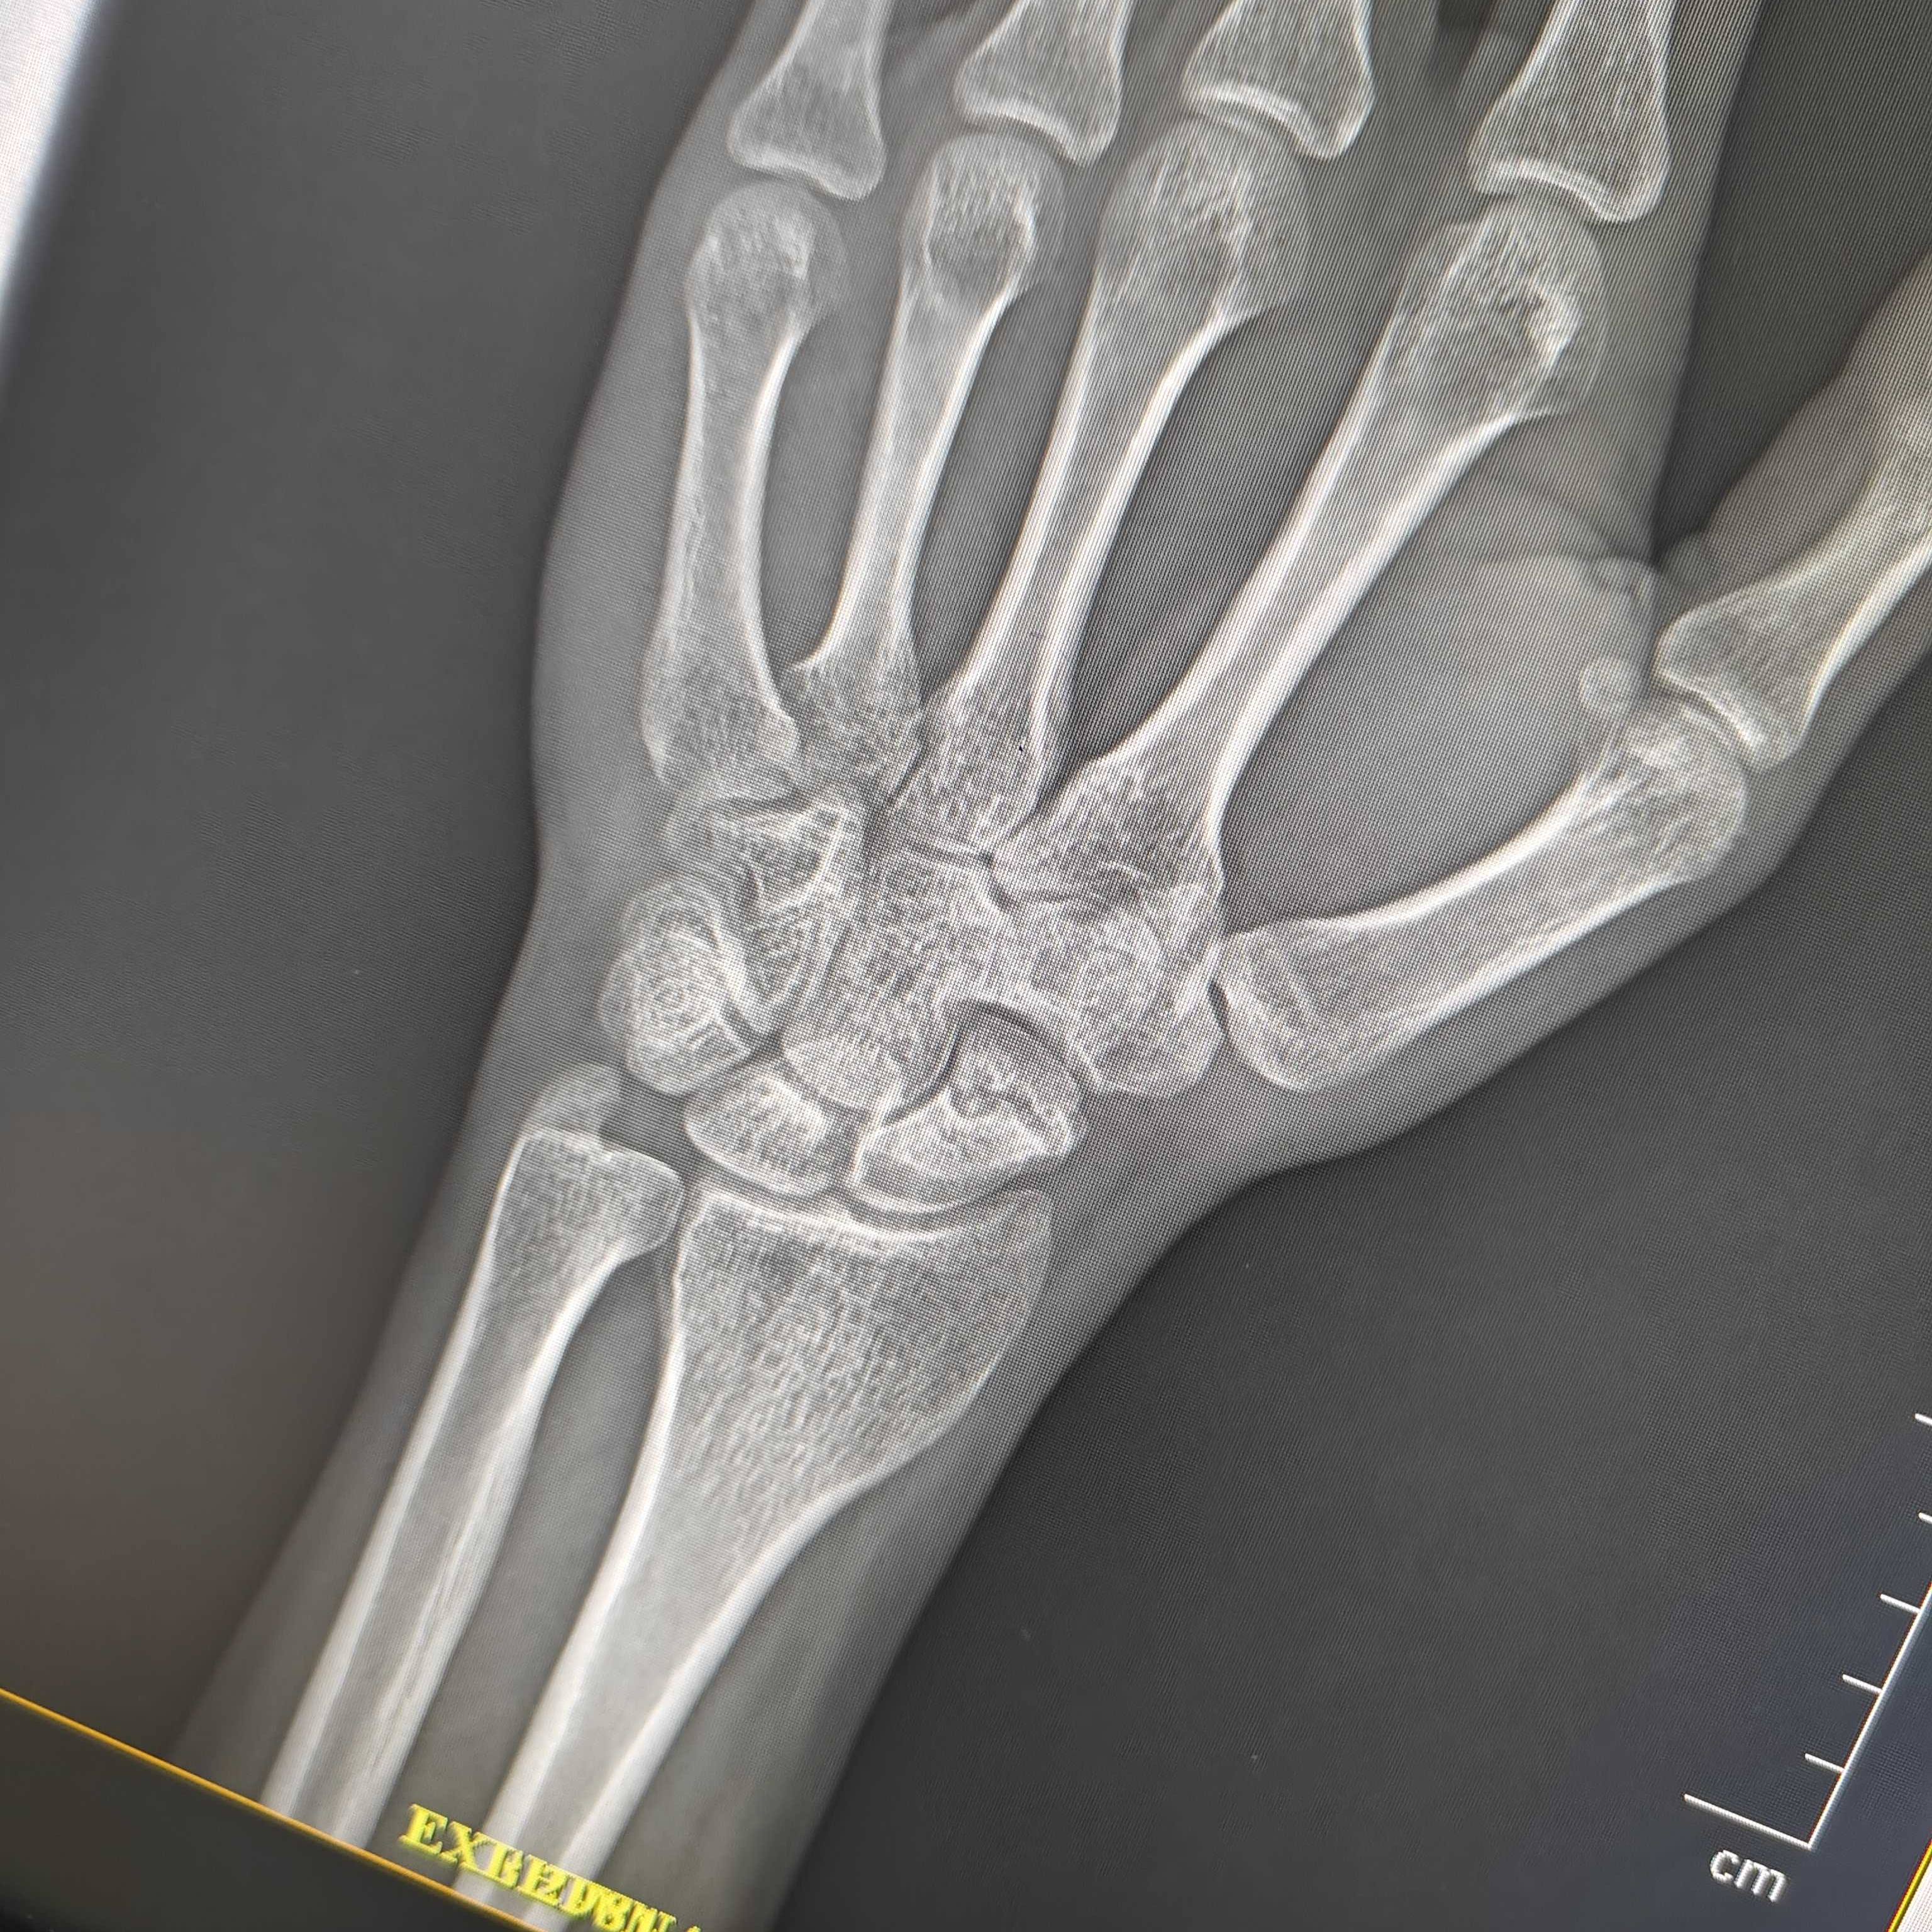

scaphoid fracture related

10-11 महीने पहले मेरा हाथ फ्रैक्चर हो गया था , पर xray में नहीं आया , फिर जब मैंने डिजिटल xray करवाया तो उसमें scaphoid fracture बताया है , तो मुझे ये पूछना था कि 10-11 महीने Old scaphoid फ्रैक्चर का कौनसा आपरेशन होगा , स्क्रू लगाया जाएगा या फिर हड्डी ही चेंज की jayegi